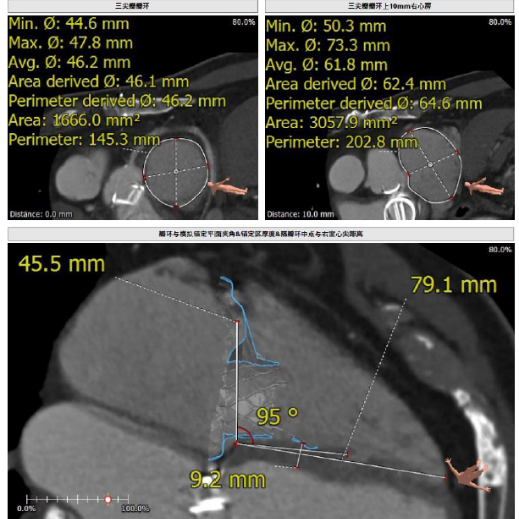

接受本次治療的是一例三尖瓣重度反流的患者,NYHA心功能Ⅲ級(jí)。主訴“反復(fù)活動(dòng)后氣促1年,下肢水腫4個(gè)月”。入院N末端B型腦鈉肽前體(NT-proBNP)3161pg/ml。心電圖提示:心房顫動(dòng),ST-T改變。術(shù)前超聲提示:重度三尖瓣關(guān)閉不全,右心房擴(kuò)大,三尖瓣收縮期位移(TAPSE)14mm,左房增大,左室收縮功能正常低值,主動(dòng)脈瓣、二尖瓣機(jī)械瓣功能良好。術(shù)前CT評(píng)估(圖1):三尖瓣瓣環(huán)(周長(zhǎng)換算直徑)大小為46.2mm;入路血管無(wú)嚴(yán)重迂曲,無(wú)鈣化;雙側(cè)冠脈有鈣化。